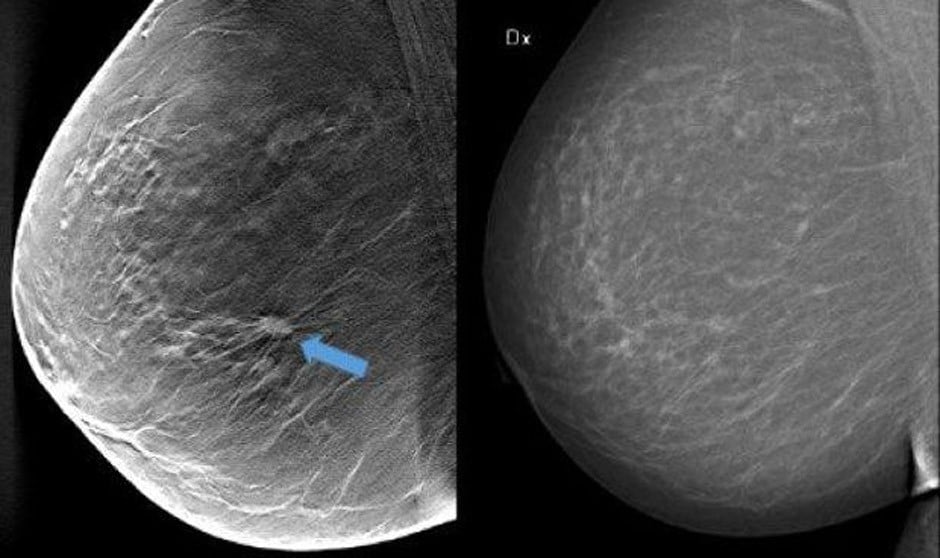

La calcificación arterial mamaria, la acumulación de calcio en la capa media de la pared arterial de la mama, está relacionada con el envejecimiento, la diabetes de tipo 2, la hipertensión y la inflamación, y es un marcador de la rigidez de las arterias. No es lo mismo que la calcificación de la capa interna de las arterias (la capa que está en contacto con la sangre), que suele darse en personas que fuman o con niveles altos de colesterol.

La calcificación de las arterias mamarias es un hallazgo común que aparece como áreas blancas en las arterias de la mama en una mamografía, sin embargo, no se cree que esté relacionado con el cáncer.

Calcificación arterial mamaria